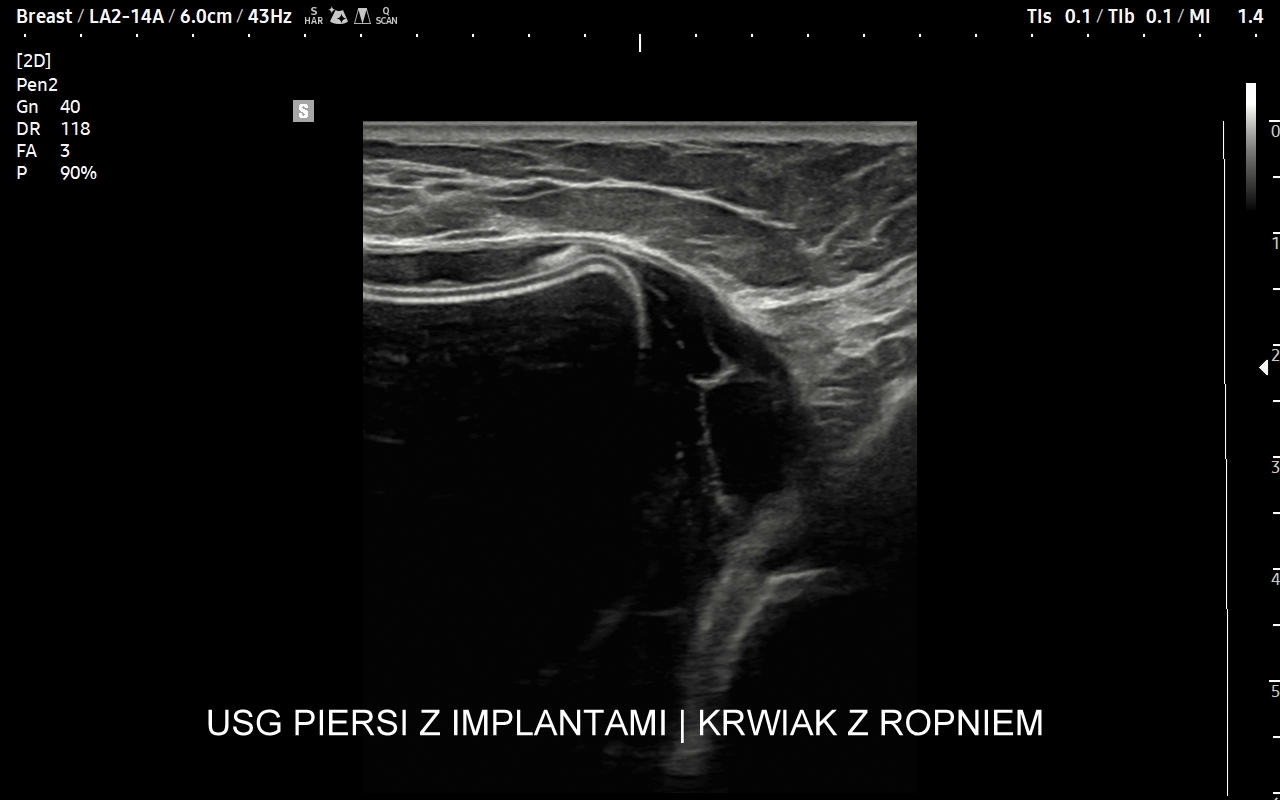

USG piersi z implantami

Badanie USG piersi z implantami jest szczególną procedurą diagnostyczną. Przeprowadza się ze wskazań wcześniej opisanych, jak w przypadku piersi bez implantów, ale także w schorzeniach ściśle związanych z implantem. Przykładami są powikłania chirurgiczne takie jak przemieszczenie się implantu, krwiak, ropne zapalenie tkanek wokół implantu, jego pęknięcie, a także wystąpienie chłoniaka BIA-ALCL (ang. breast implant associated anaplastic large cell lymphoma) jako odległego powikłania wszczepienia implantu piersi.